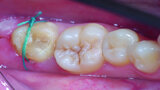

Fig. 14d: Clinical image: Control after one month.